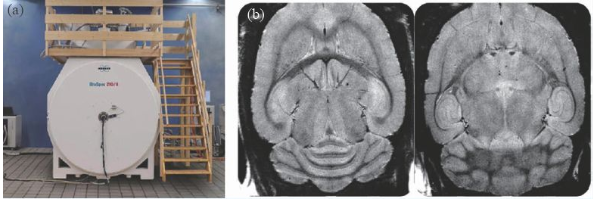

除了人體成像的超高場(chǎng)磁共振成像裝置外,用于動(dòng)物臨床前應(yīng)用的裝置在磁場(chǎng)強(qiáng)度上遠(yuǎn)遠(yuǎn)走在了前面,10 年前就出現(xiàn)了16.4 T/26 cm動(dòng)物成像MRI 機(jī),德國(guó)的Bruker公司在幾年前也推出了更高磁場(chǎng)的動(dòng)物成像機(jī)—— 21 T/11 cm動(dòng)物成像MRI機(jī)(圖8)。

image.png

圖8 (a)21 T MRI磁體;(b)大鼠的腦部高分辨率成像(分辨率26 μm)